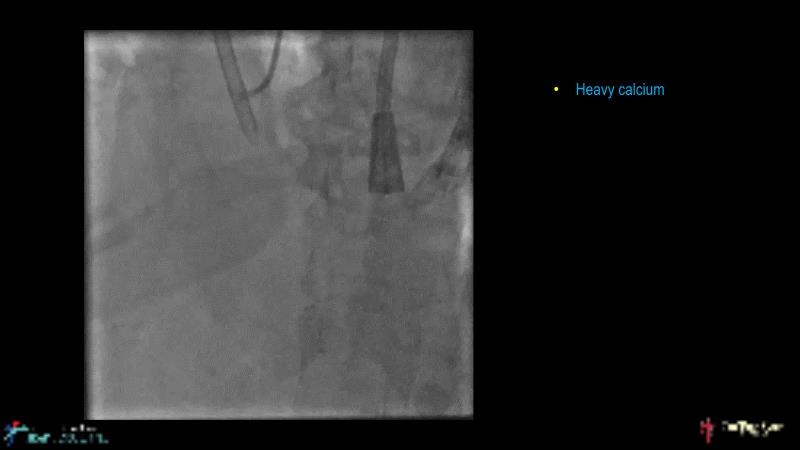

Cracking calcium: best practices to integrate intravascular lithotripsy into your calcium management algorithm

With this session, keep up to date on the evidence, trials and outcome data for intravascular lithotripsy in severely calcified lesions. Learn how to use this technique in real-world patients and understand its role in the treatment algorithm for severely calcified coronary lesions.

- To know the evidence, trials and outcome data for intravascular lithotripsy in severely calcified lesions